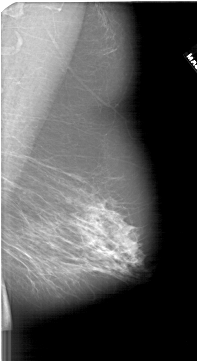

A_1666_1.RIGHT_MLO

RIGHT_CC LINES 6616 PIXELS_PER_LINE 3316 BITS_PER_PIXEL 12 RESOLUTION 43.5 NON_OVERLAY

RIGHT_MLO LINES 6496 PIXELS_PER_LINE 3541 BITS_PER_PIXEL 12 RESOLUTION 43.5 NON_OVERLAY